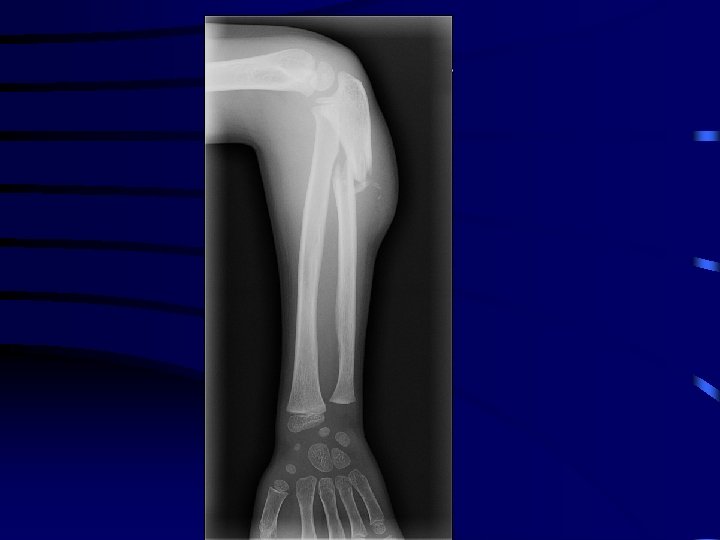

4 La fracture plastique • L'os présente une déformation sans trait de fracture. • L'exemple le plus fréquent est la fracture plastique de l'ulna (cubitus) associée à une luxation de la tête radiale. .

La fracture plastique